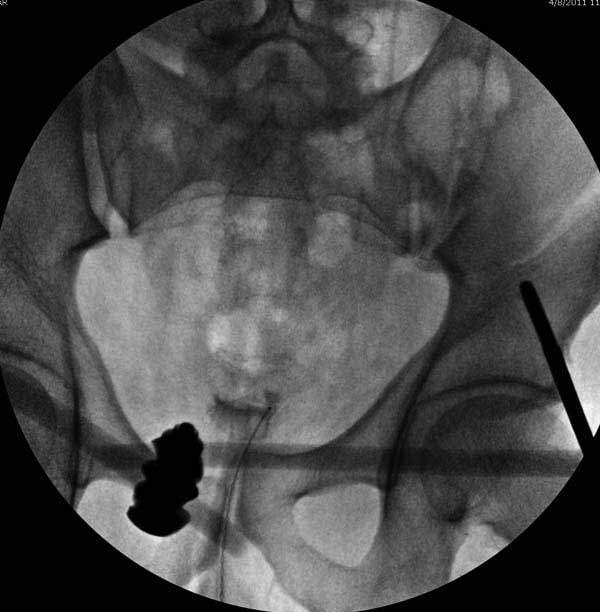

Представлены снимки техники проведения стержней. Через место прикрепления прямой мышцы в Inferior Iliac Spine в направления вырезки создается жесткость. Weber clamp изнутри таза для репозиции, и фиксация после репозиции перелома крыла подвздошной кости. Наружный аппарат удален, нагрузка предполагается через два месяца.

Здесь представлен случай 38 летнего больного (падение с высоты 9 метров) с нарушением тазового кольца. При поступлении для стабилизации передне-нижний аппарат наружной фиксации и на 6й день, вчера, операция из двух доступов.